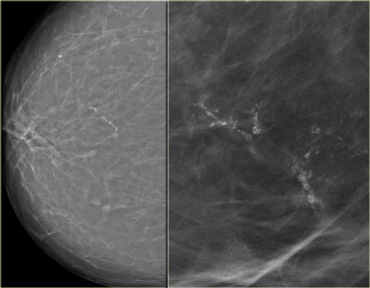

Fine pleomorphic calcifications in a segmental distribution in combination with an irregular mass (Bi-RADS 5) Fine pleomorphic calcifications in a segmental distribution in combination with an irregular mass (Bi-RADS 5)

On the left a mammogram demonstrating two forms of calcifications.

There are some round typically benign calcifications.

The most conspicious calcifications however are the fine pleomorphic calcifications.

They have a segmental distribution.

In the presence of the mass these calcifications were classified as Bi-RADS 5.

Biopsy demonstrated an extensive high grade DCIS with an invasive carcinoma.